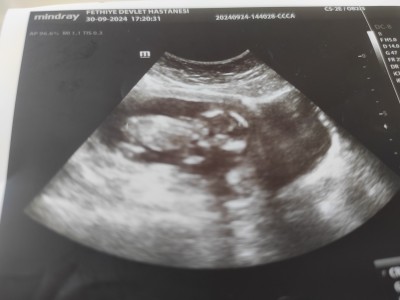

30 Eylül 2024 Hamilelik Dönemi Genel kategorisinde (16 puan) sordu

13+4 cinsiyet tahmini yapabilirsiniz misiniz

Gebelik haftası 13

Evet tahmini erkek dedi  4hafta sonraki kontrolde netlescek

Bugün gittim 13+4  doktor tahmini erkek dedi

Anladım canım son tahminler doğru çıkıyor genellikle 16 haftalık net ogrenirsiniz